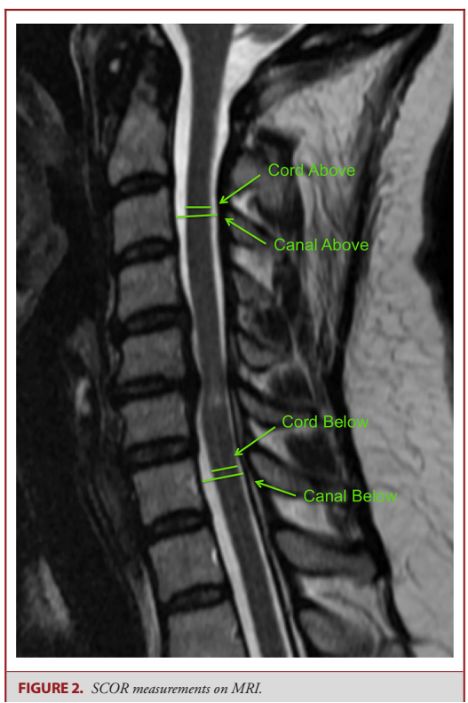

33.多中心队列研究先天性颈椎管狭窄患者退行性脊髓型颈椎病:基于核磁共振诊断原则的报告

Congenital Cervical Spine Stenosis in a Multicenter Global Cohort of Patients With Degenerative Cervical Myelopathy: An Ambispective Report Based on a Magnetic Resonance Imaging Diagnostic Criterion.

PMID: 29462433 DOI: 10.1093/neuros/nyx521

先天性颈椎管狭窄是急性脊髓损伤和发展为退行性脊髓型颈椎病的危险因素。本研究的目的是开发基于磁共振成像(MRI)的标准来诊断先前存在的先天性颈椎管狭窄(CSS),并评价CSS患者与无CSS患者间的差异。

该研究共纳入349例手术的脊髓型颈椎病患者和27例对照组患者,结果发现:脊髓占位比(SCOR,通过在非压迫部位测量椎管和脊髓前后径计算出)≥70%是诊断CSS的有效标准。CSS患者在较年轻的年龄发展为脊髓型颈椎病,并且神经功能的损伤和致残程度更严重。尽管如此,与无CSS的脊髓型颈椎病患者相比,CSS患者在症状持续时间,MRI表现及手术效果方面与其相似。

![]()